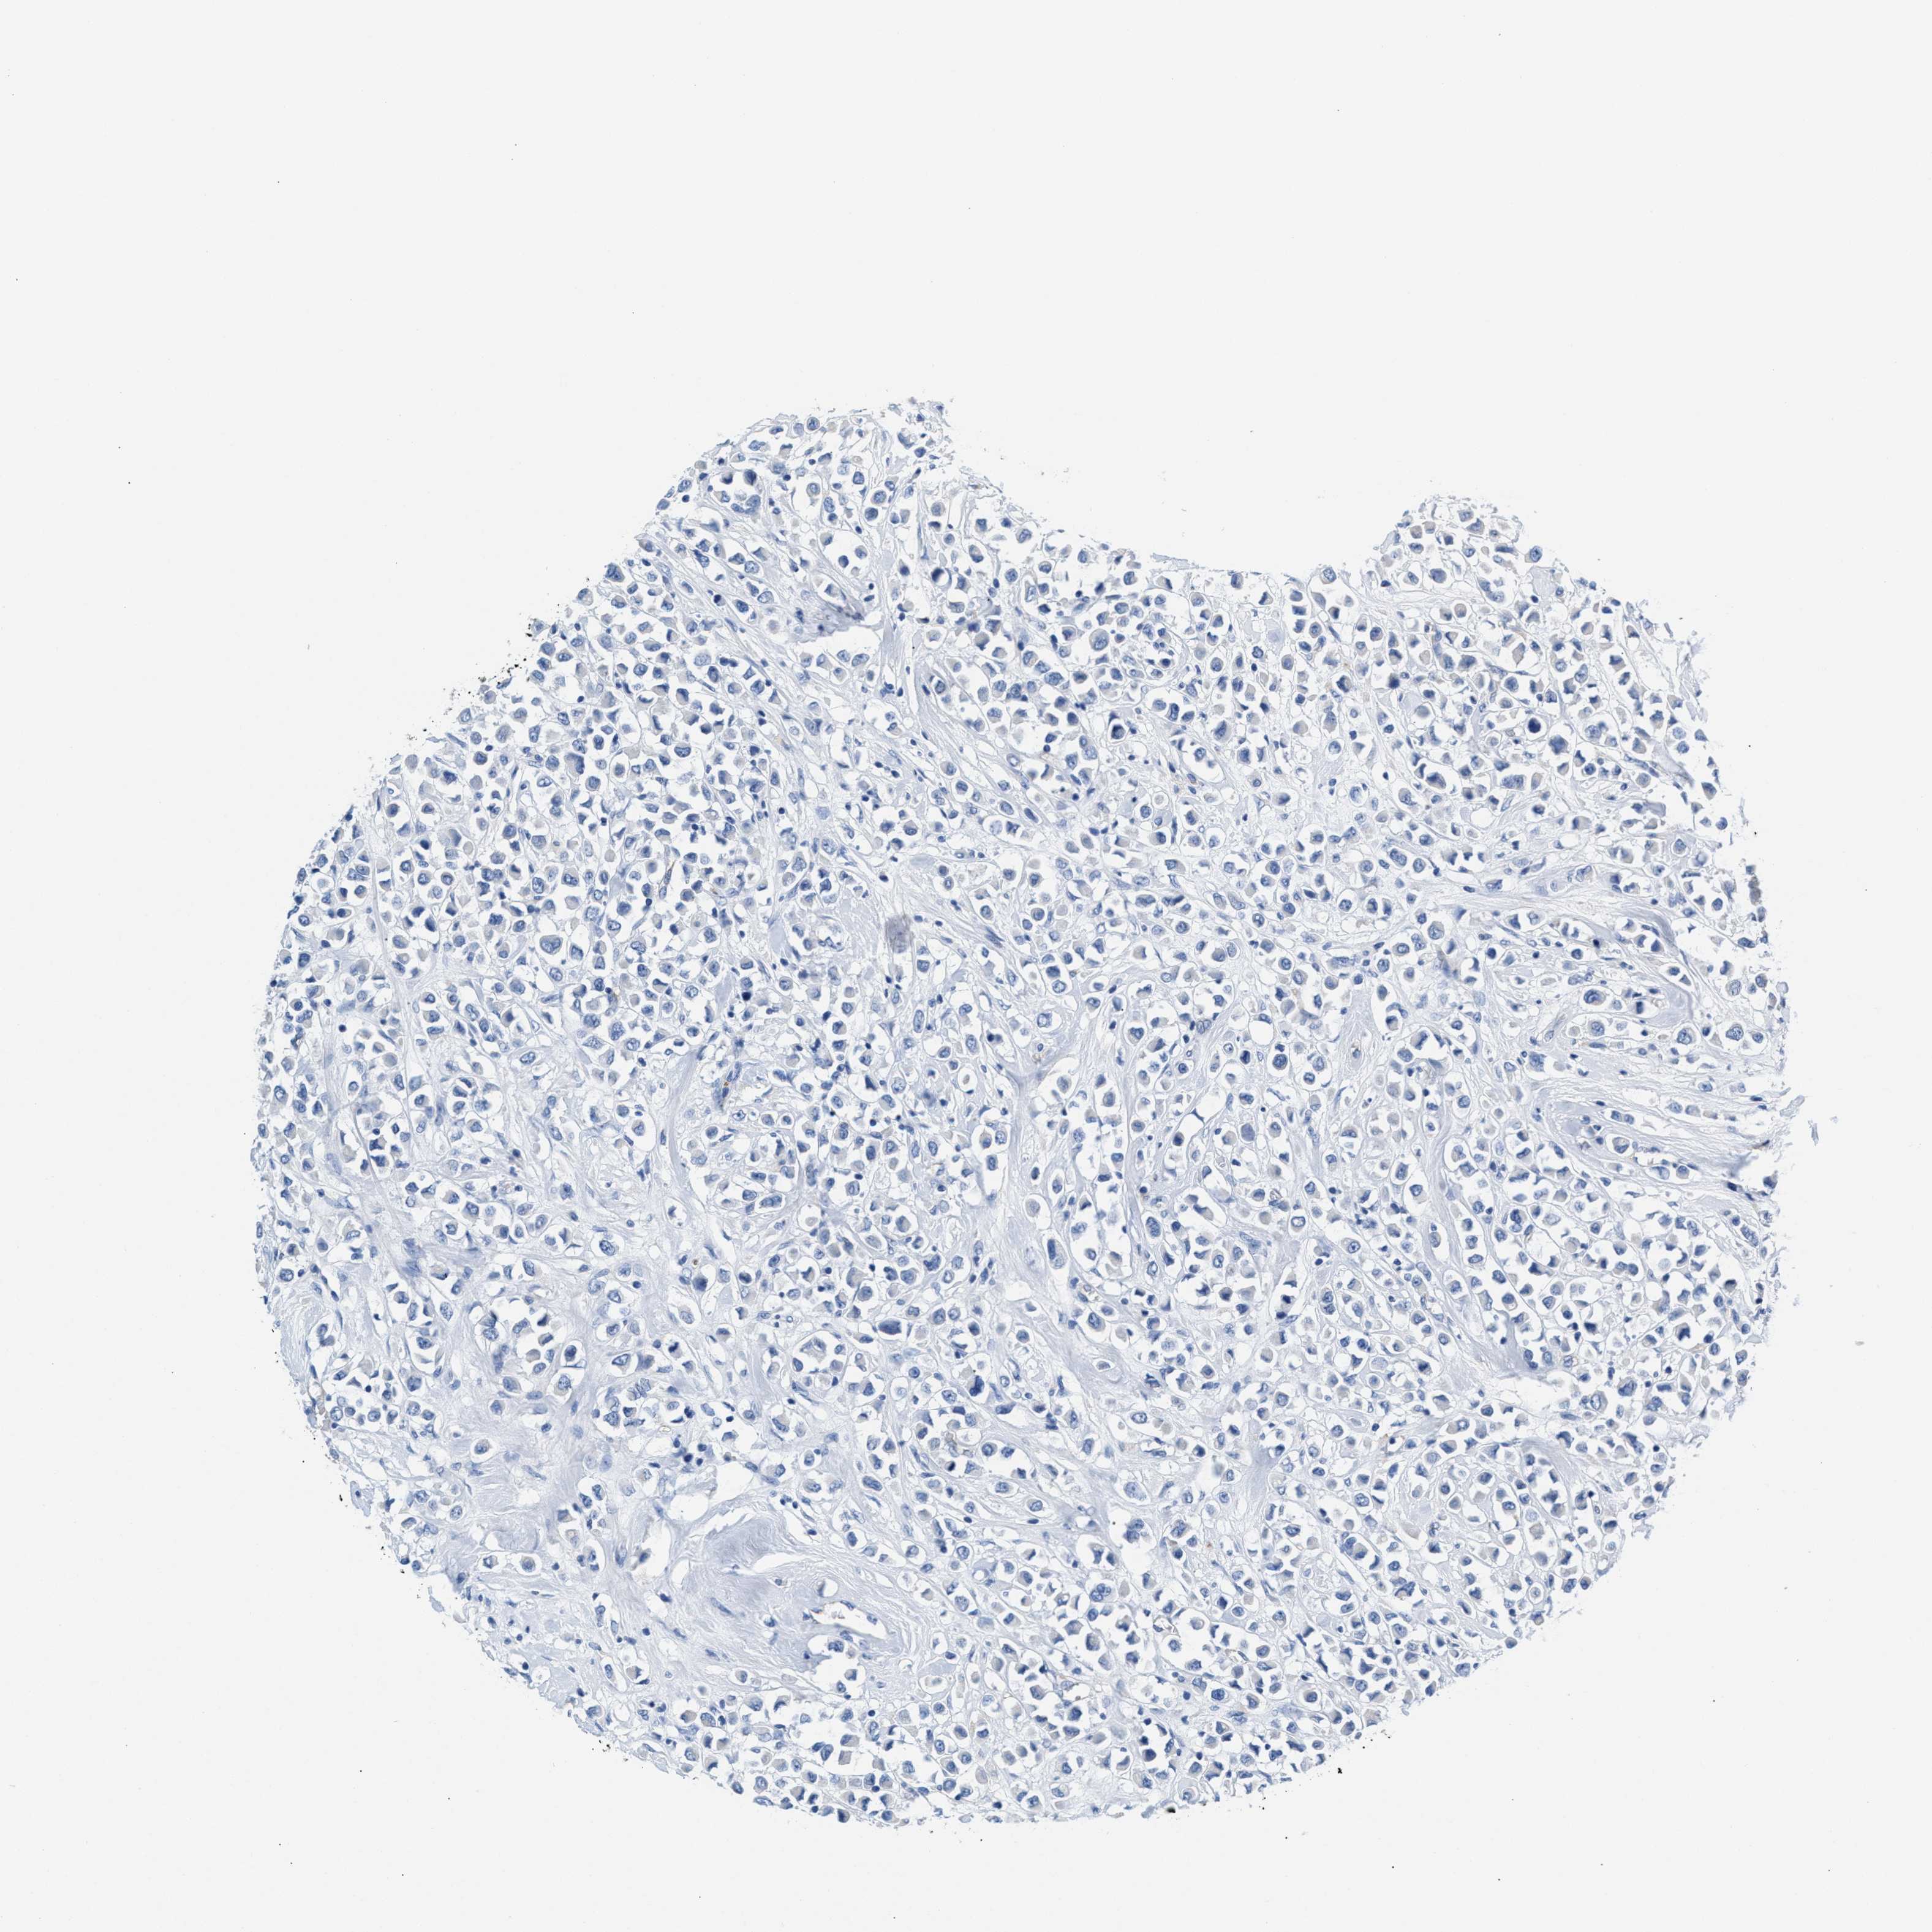

CANCER BREAST CANCER Show tissue menu

BRCA TCGA BRCA VALIDATION PROTEIN EXPRESSION